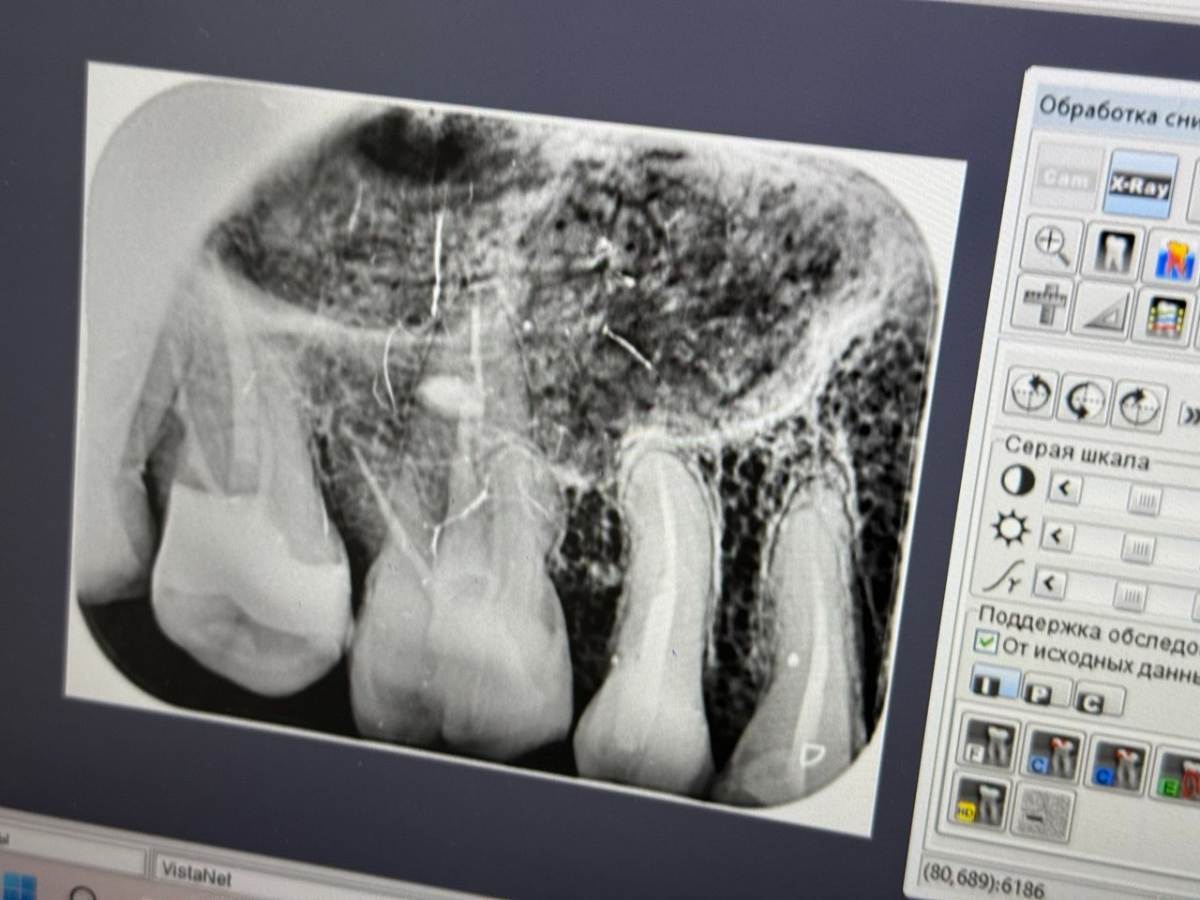

Sergey32132 Опубликовано 28 ноября, 2025 Автор Поделиться Опубликовано 28 ноября, 2025 (изменено) апдейт: Сегодня пошел таки решил перелечить, правда врач с клиники где мне прошлые разы спасали не спасаемое, позвонили сказали что заболел, смог попасть в другую, здесь я первый раз, но тоже выбирал где есть микроскоп и работают с ним, трещины сегодня сказали не увидели, сегодня каналы а следующий раз реставрацию, но я сфоткал для себя снимок, и когда вышел уже обратил внимание на ход гуттаперчи в бок, подскажите пожалуйста, это судя по всему перфорация ? Если да, во всех ли случаях плохой прогноз ? Изменено 28 ноября, 2025 пользователем Sergey32132 Ссылка на комментарий

сирена Опубликовано 1 декабря, 2025 Поделиться Опубликовано 1 декабря, 2025 Нет, это второй корень. 1 Ссылка на комментарий